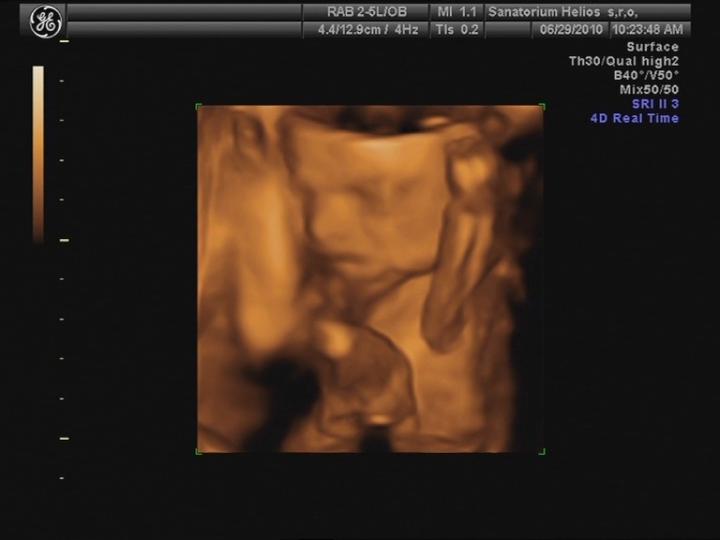

Byla jsem na UTZ, odpovídáme 10+4 tt a všechno je v pořádku... 🙂